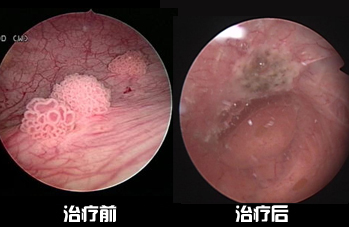

成功案例

膀胱肿瘤

膀胱炎